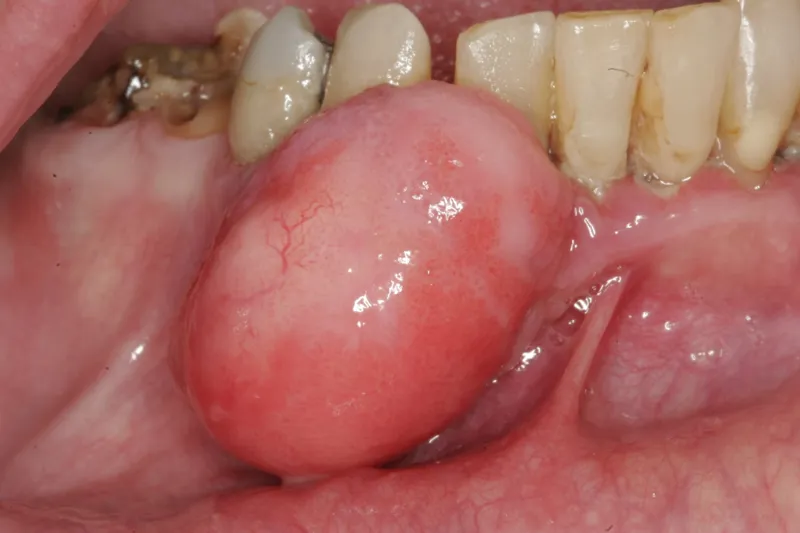

PATIENTTILFÆLDE – I denne artikel præsenteres en 69-årig kvinde med en eksofytisk gingival forandring i underkæbens front. Forandringen excideredes, og histologisk undersøgelse viste kalcificerende fibroblastisk granulom. Læsionen recidiverede flere gange, indtil en radikal tilgang blev anlagt, og tilstødende tænder blev ekstraheret.

Kalcificerende fibroblastisk granulom er en relativt hyppigt forekommende gingival hyperplasi med stort vækstpotentiale og en relativt høj recidivfrekvens. Forandringen er oftest uden symptomer, men kan give gener, når den tiltager i størrelse. Det kliniske udseende og den undertiden hurtige vækst kan foranledige patienten til at mistænke en ondartet tilstand. Det er vigtigt, at der stilles en histologisk diagnose. Overvejelserne ved excision bør gå på at eliminere mulige irritamenter og fjerne afficeret væv for at undgå recidiv. Nærværende artikel beskriver et sjældent tilfælde, hvor en radikal tilgang med ekstraktion af tænder var en forudsætning for en succesfuld behandling.